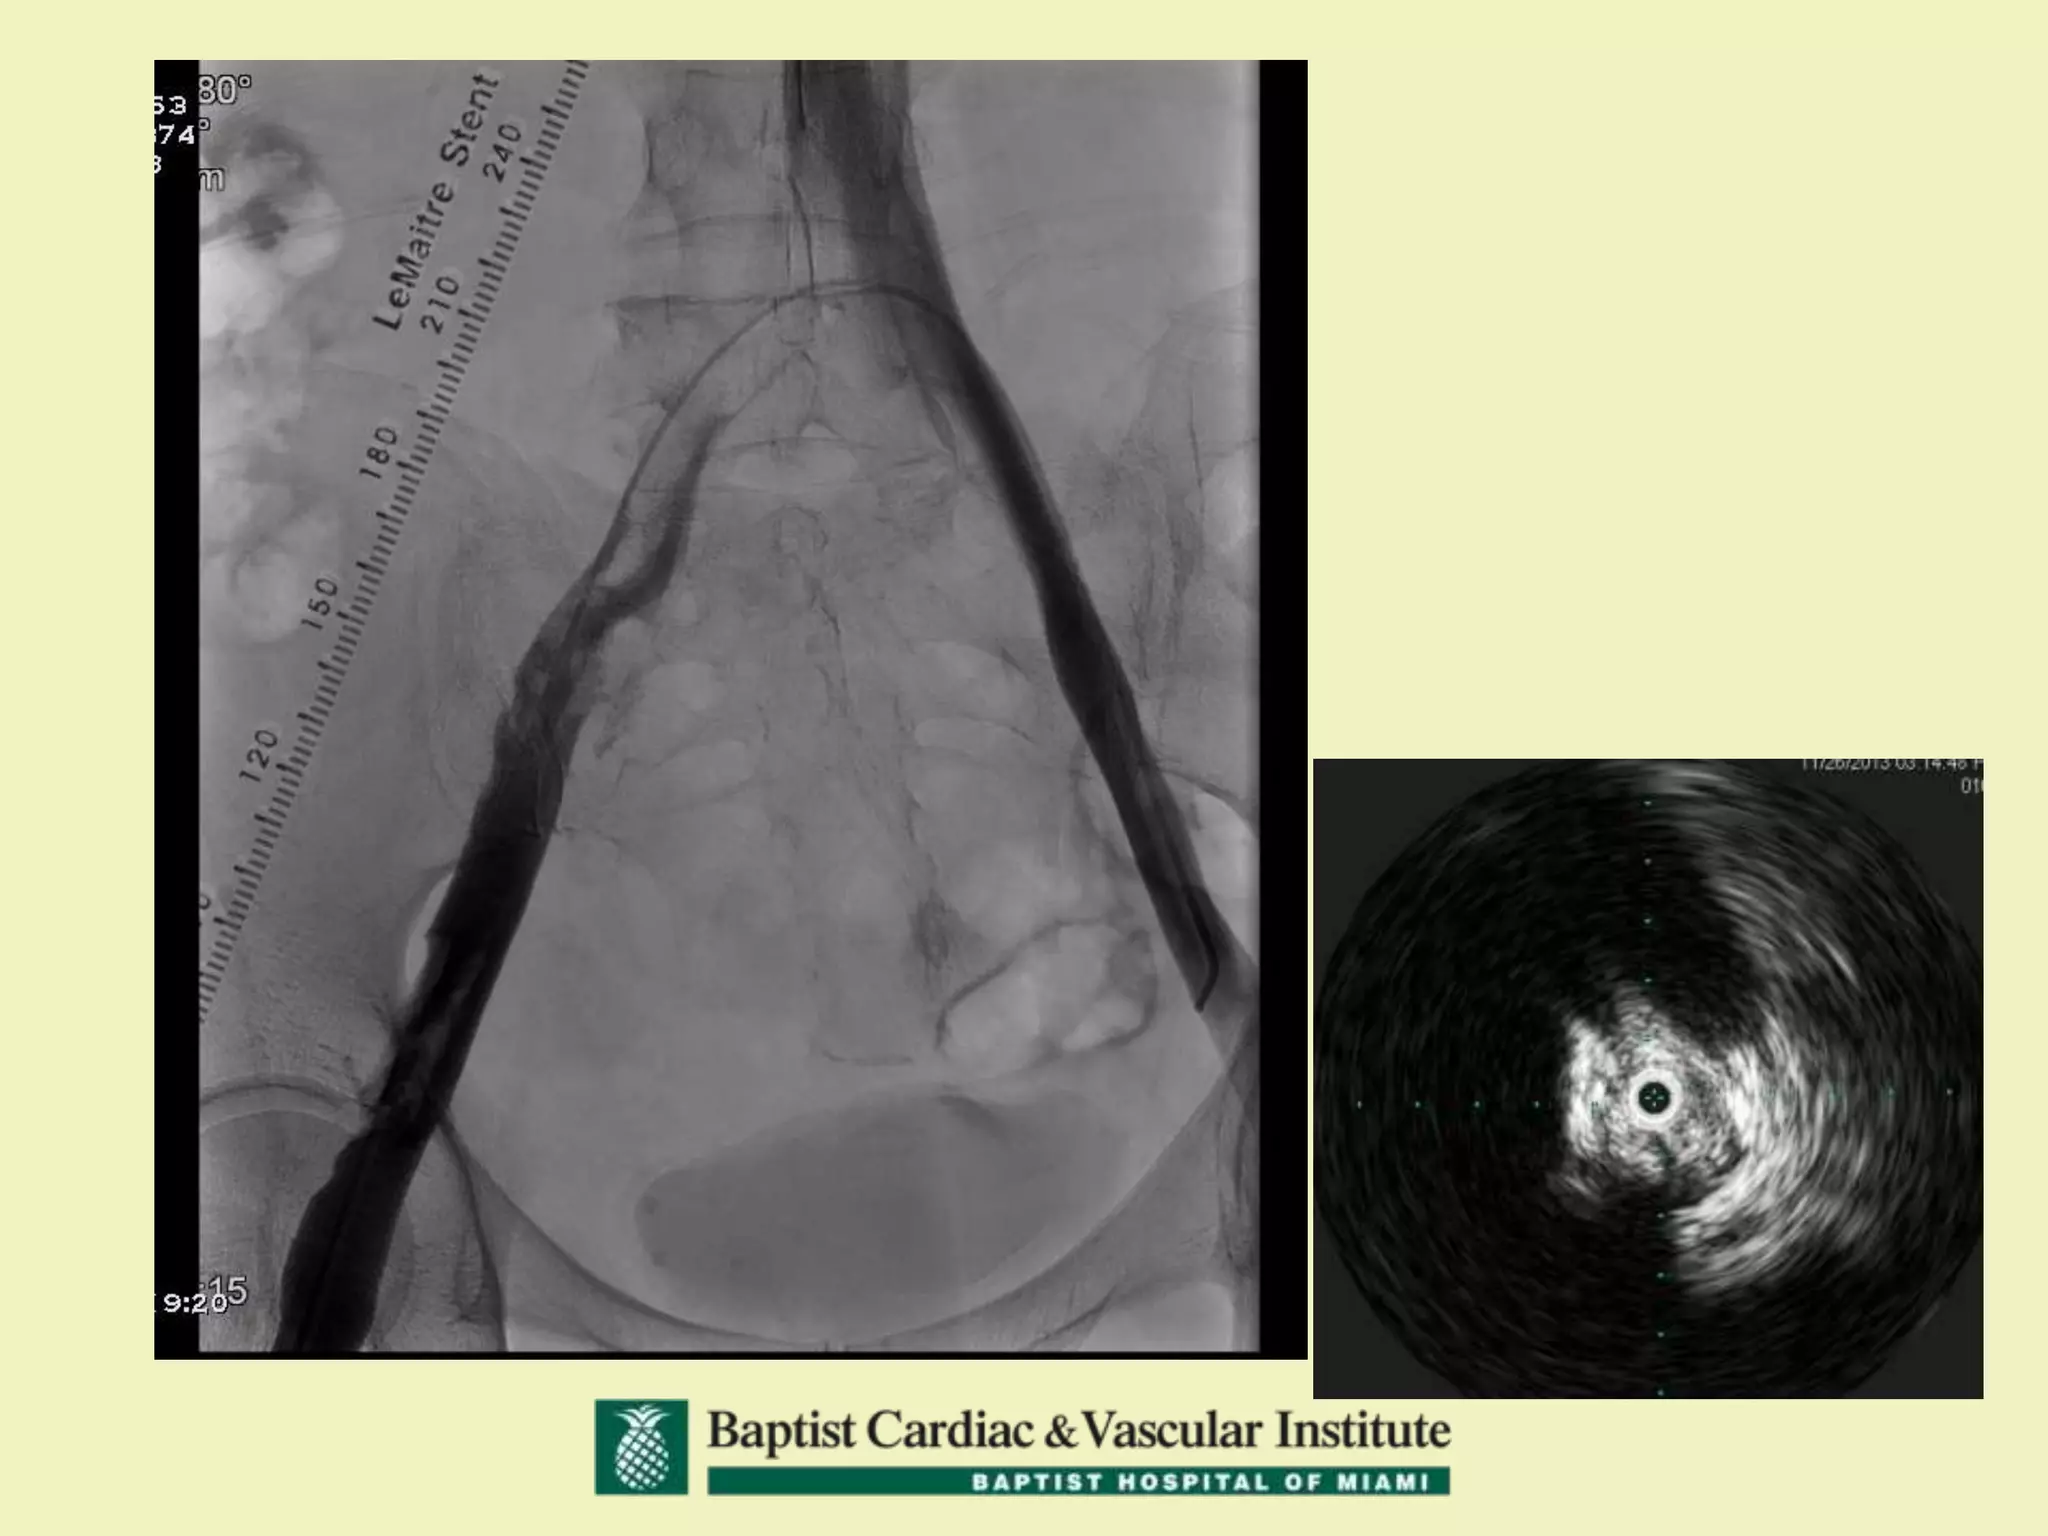

68 yo with Left Leg Swelling and

Left DVT

68 yo withLeft Leg Swelling and Left DVT